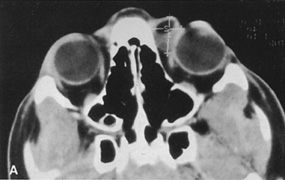

Magnetic resonance imaging is useful in selected cases, especially when evaluating the orbital cranial junction. Significant bony artifact and a lack of orbital fat in the orbital apex make CT scan resolution of the orbital apex structures poor. Because cortical bone has low signal on MRI, there is no bone artifact when viewing the orbital apex on MRI. The lack of intervening fat in the apex to provide contrast is overcome on MRI because contrast is provided by the individual nuclear characteristics of each tissue so that the orbital apex structures are visualized well. Consequently, conditions that affect the optic nerve and chiasm, such as optic nerve meningioma and glioma, generally are evaluated with MRI rather than CT scan (Fig. 2).

Fig. 2. A. Axial orbital CT scan of right optic nerve meningioma. Note lack of detail in orbital apex. B. Axial orbital MR image, same patient. Note increased detail in orbital apex owing to lack of bone artifact. C. MRI with gadolinium contrast. Note extension into brain not easily appreciated with CT scanning or MRI without contrast.